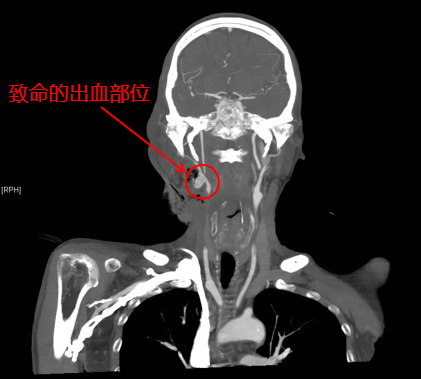

患者影像

耳鼻咽喉头颈外科主治医师陈雯婧、血管外科主治医师曹战江前来急诊会诊。患者的增强CT影像显示,出血部位近动脉血管,考虑肿瘤压迫动脉导致出血。病情急而重,陈雯婧请示科主任叶京英后,认为该患者下咽癌已属晚期,不具备根治性手术机会,动脉栓塞止血应为优先考虑方案。曹战江向科主任吴巍巍汇报了病情,决定立即为该患者进行动脉栓塞手术。